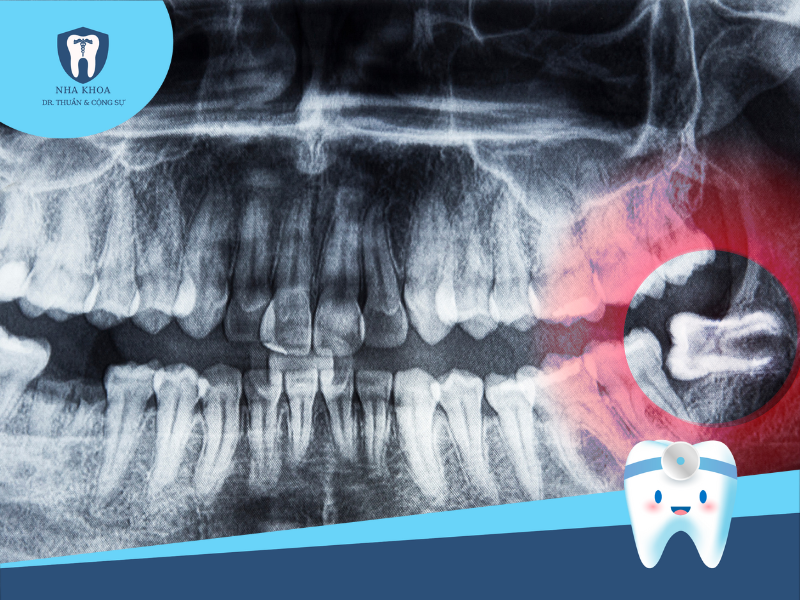

Bước 1: Khám tổng quát và chụp phim X-quang

Đây là bước đầu tiên nhưng cũng rất quan trọng trong quy trình nhổ răng khôn. Theo đó, nha sĩ sẽ thực hiện các biện pháp thăm khám để đánh giá tình trạng tổng quát, cũng như khám kĩ để xem xét tình trạng, vị trí, mức độ tổn thương... của răng. Sau đó, bác sĩ sẽ cho bệnh nhân chụp phim X-quang hàm răng để đánh giá hình ảnh chính xác về tư thế và vị trí răng khôn mọc, giúp nha sĩ nắm rõ và xây dựng kế hoạch nhổ răng phù hợp và ít sang chấn cho người bệnh.

Chụp x-quang xác định vị trí của răng khôn